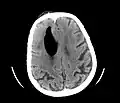

CT scans of patients with a tension pneumocephalus typically show air that compresses the frontal lobes of the brain, which results in a tented appearance of the brain in the skull known as the Mount Fuji sign.[1][2][3] The name is derived from the resemblance of the brain to Mount Fuji in Japan, a volcano known for its symmetrical cone. In typical cases, there is a symmetrical depression near the midline (such as the crater of a volcano), due to intact bridging veins.[3] Its occurrence seems to be limited to tension pneumocephalus (not occurring in pneumocephalus without tension).[4] The sign was first described by a team of Japanese neurosurgeons.[5]

Pneumocephalus has also been shown to follow neurosurgical procedures such as deep brain stimulation and hematoma evacuation (e.g., chronic subdural hematoma[6]), where while seemingly innocuous to the patient, may cause brain shift, subsequent stereotactic inaccuracy, and even another surgical intervention.[7][8] Regarding chronic subdural hematoma (CSDH) surgery, a postoperative volume of pneumocephalus greater than 15mL puts a patient at increased risk of CSDH recurrence; in fact, for every milliliter of air entering the cranial cavity after CSDH evacuation, the recurrence risk increases by 4%.[9] Efforts are made by neurosurgeons to reduce pneumocephalus volume during surgery, and thus, subsequent brain shift.